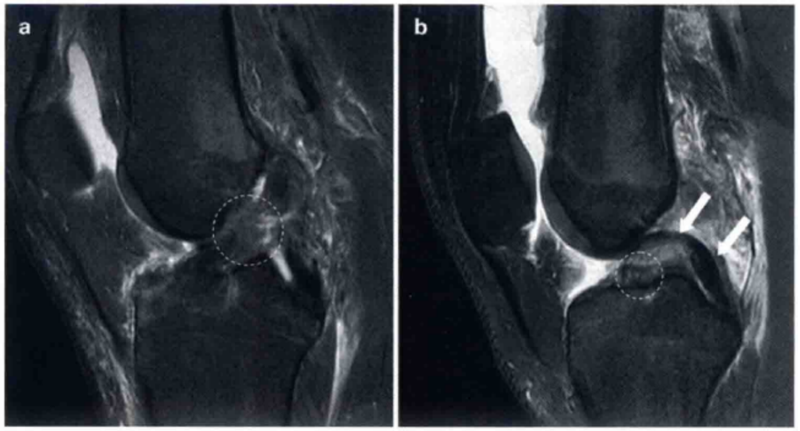

图1 a和b分别显示的是在T2图像中矢状位和轴位正常的ACL。

a显示绷紧,可见明显的ACL低信号(白色箭头)。在a中也显示正常的胫骨附着点(圆形标记)。b显示在水平面上正常的股骨附着点

图2 a和b显示的为2个不同患者ACL损伤的表现。

a显示韧带呈波浪形,并且实质部中部不连续(圆形标记)。在b中直接可以看到ACL胫骨侧的残端(圆形标记)。标记了正常的PCL(白色箭头)